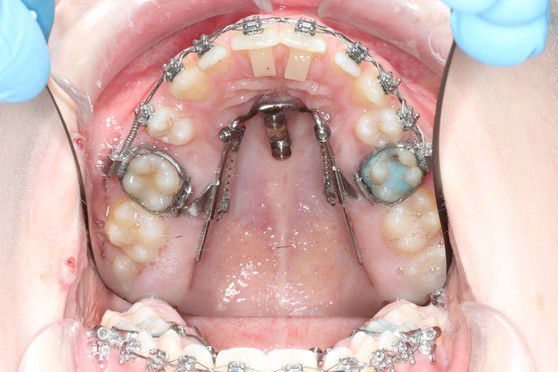

De indsættes i knoglen under lokalbedøvelse.

De kan sidde enten i den ene side eller i ganen.

Ved hjælp af skruerne kan man flytte enten en eller flere tænder uden at resten af tænderne belastes.